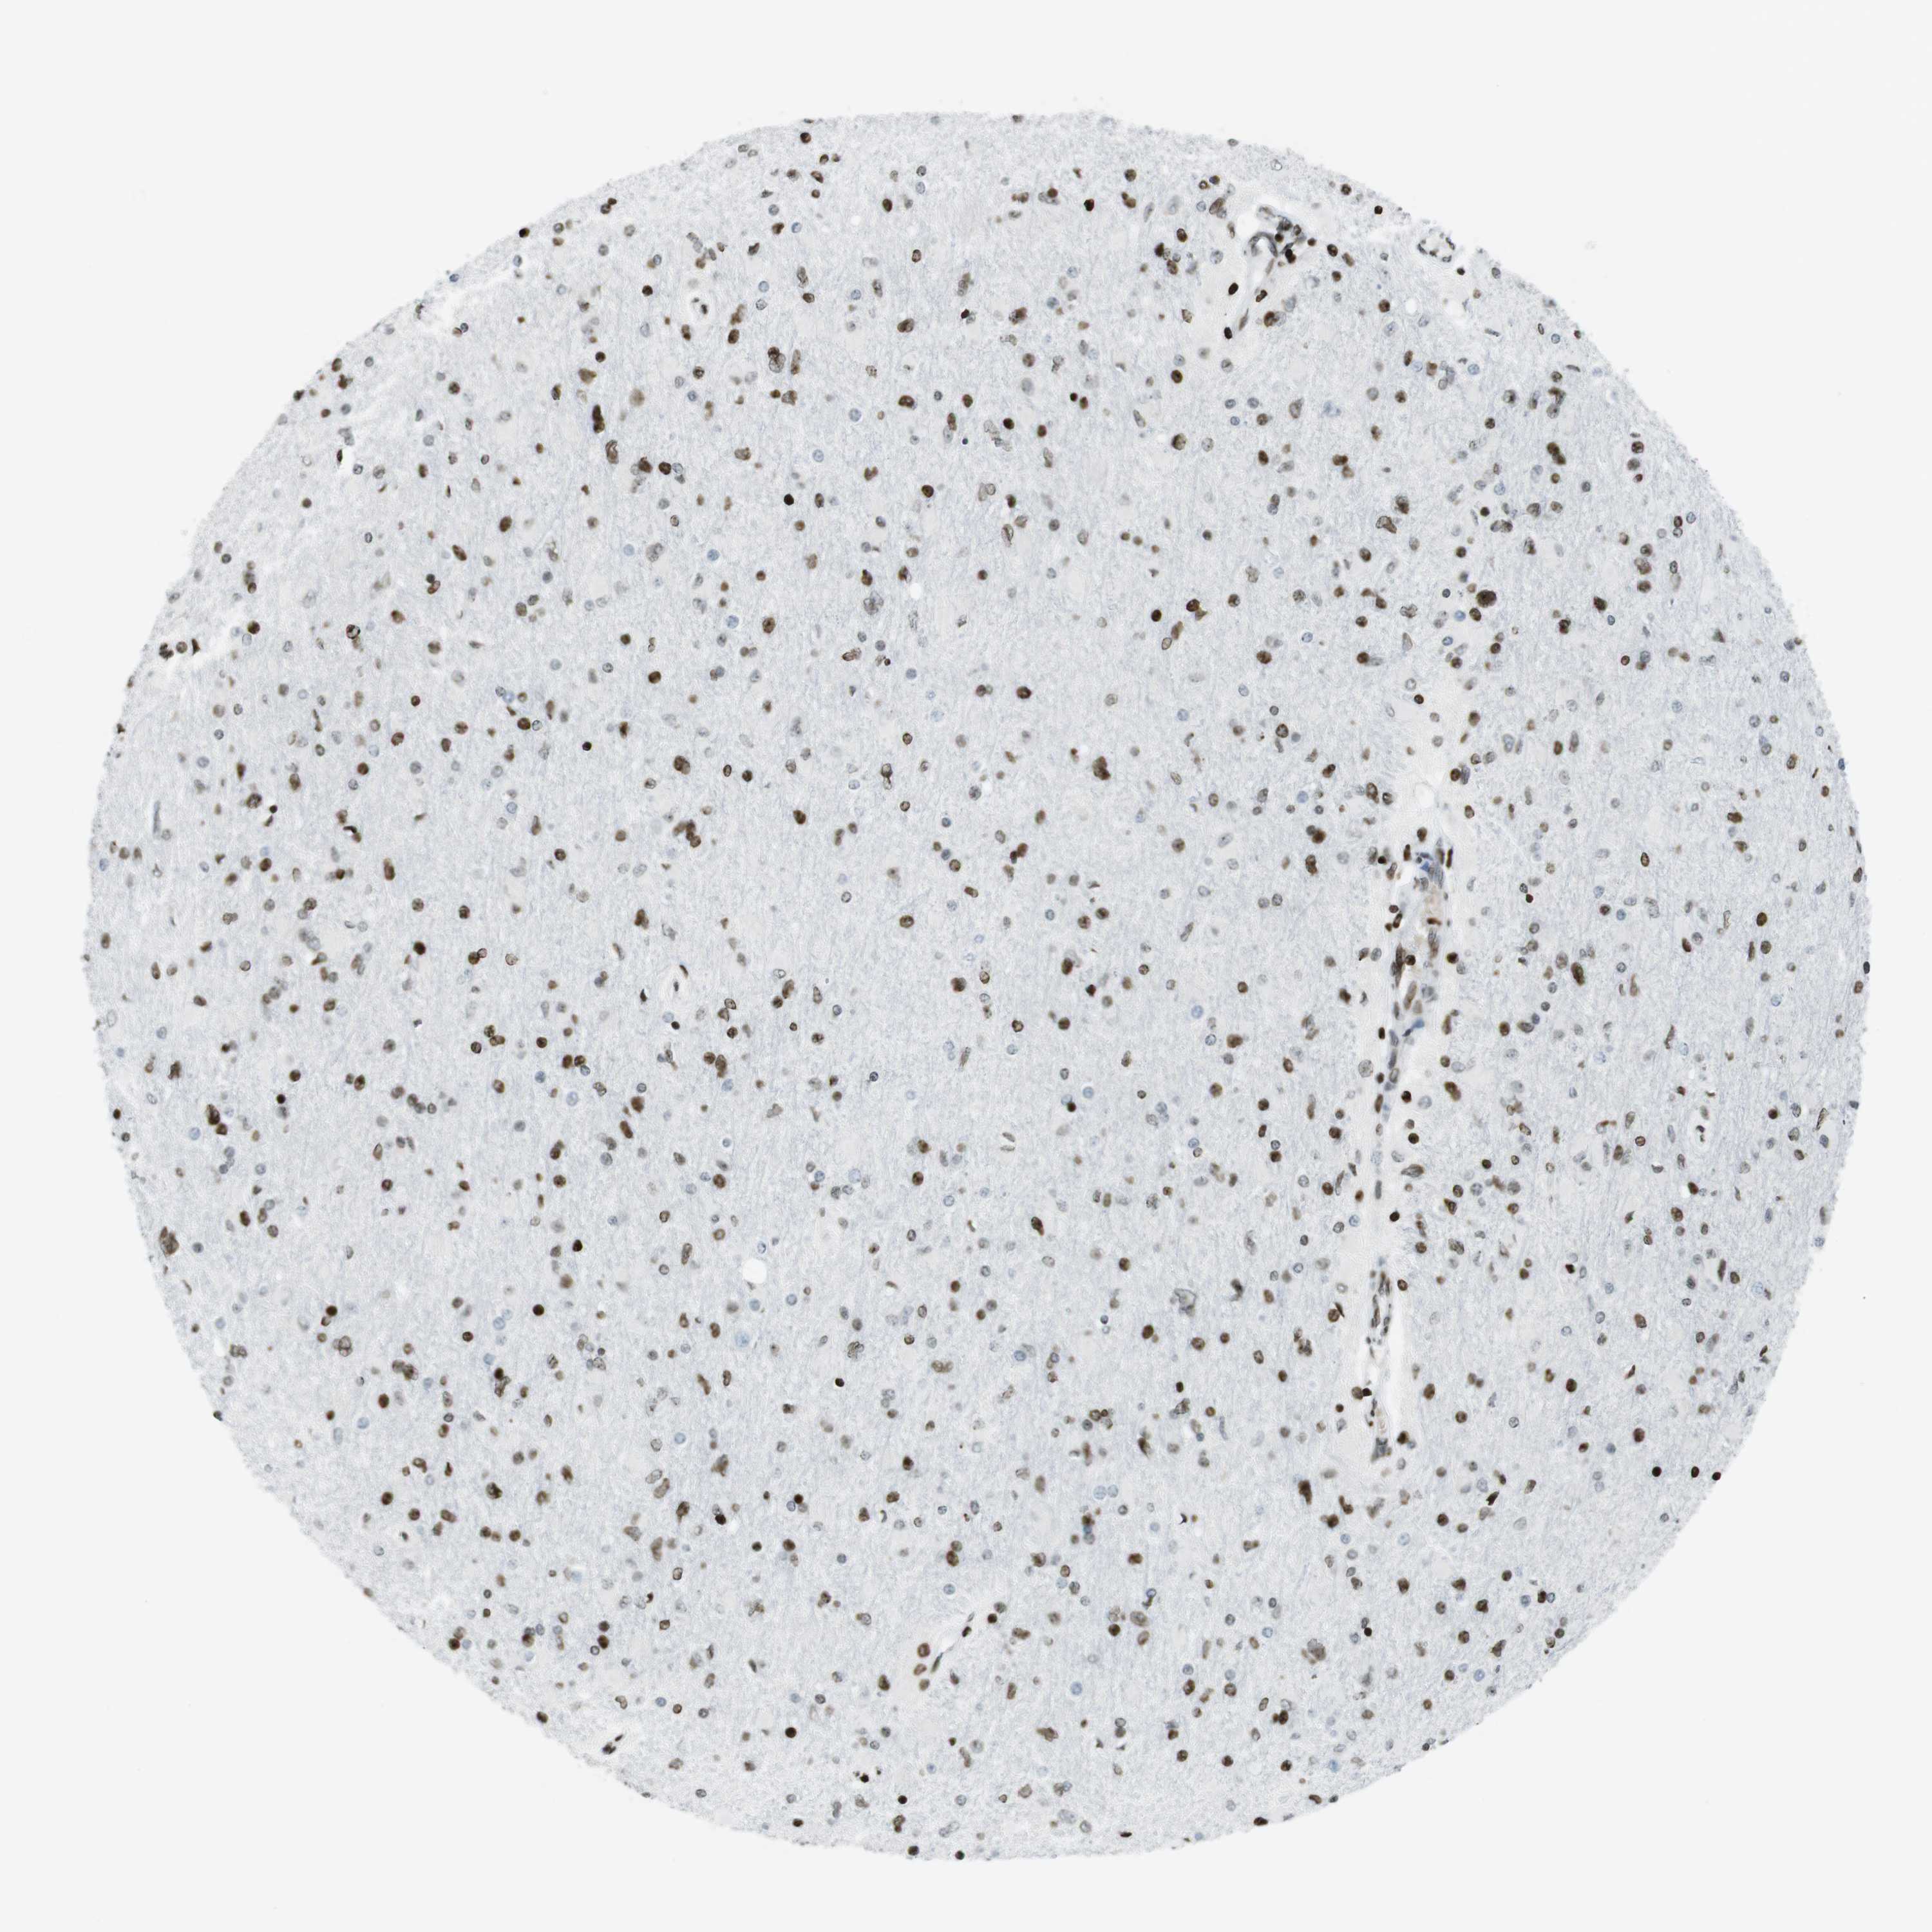

GLIOMA - Protein expressioni

A mouse-over function shows sample information and annotation data. Click on an image to view it in a full screen mode. Samples can be filtered based on level of antibody staining by selecting one or several of the following categories: high, medium, low and not detected. The assay and annotation is described here.

Note that samples used for immunohistochemistry by the Human Protein Atlas do not correspond to samples in the TCGA dataset.

Antibody stainingi

Antibody staining in the annotated cell types in the current human tissue is reported as not detected, low, medium, or high, based on conventional immunohistochemistry profiling in selected tissues. This score is based on the combination of the staining intensity and fraction of stained cells.

Each image is clickable and will lead to virtual microscopy that enables deeper exploration of all samples and also displays staining intensity scores, fraction scores and subcellular localization as well as patient and tissue information for each sample.

Antibody HPA041189

Antibody CAB012242

Staining

High

Medium

Low

Not detected

Intensity

Strong

Moderate

Weak

Negative

Quantity

>75%

75%-25%

<25%

None

Location

Nuclear

Cytoplasmic/membranous

Cytoplasmic/membranous,nuclear

Glioma, malignant, High grade

Glioma, malignant, Low grade